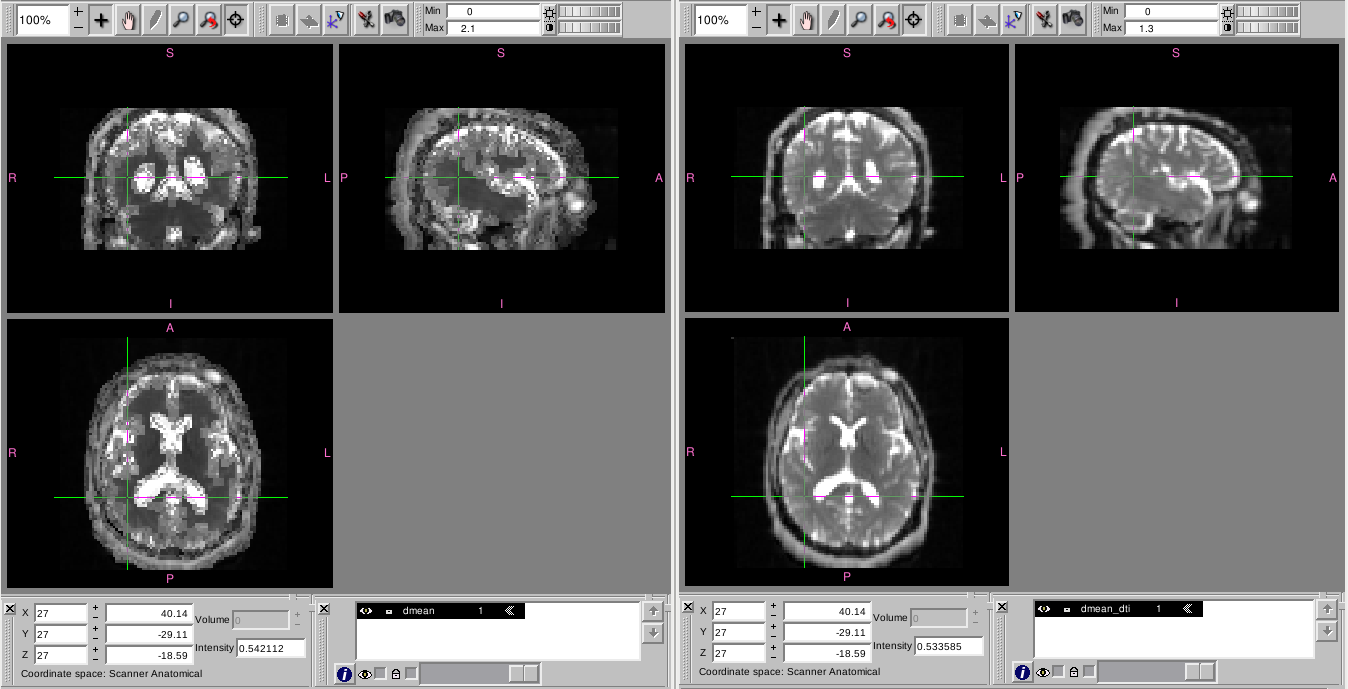

the maps obtained with the dti module look normal, but those created with the dki model have larger values in gray matter and smaller values in white matter, they look very odd to me (my understanding is that the dmean and fa should look very similar when obtained with dti or with dki).

I am attaching a picture to show the dmean maps.